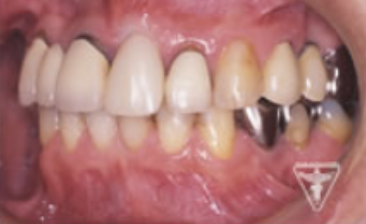

治療過程

根破折の為抜歯、審美的に抜いた部位が陥没しない様に処置しました。

抜歯後、歯周病処置、歯内療法処置、咬合高径改善、プロビジュナルレストレーションを経て最終補綴をおこないました。